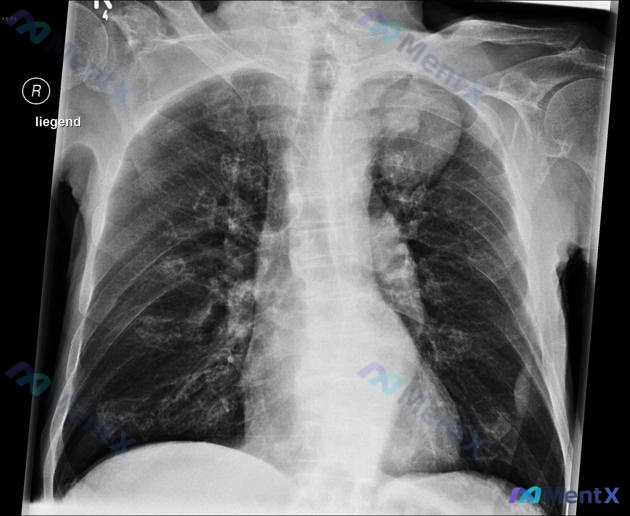

看到一个很典型的病例,整理了资料和思路,和大家分享一下。 病例基本信息 - 患者:68岁男性,因1小时前倒地、四肢剧烈颤抖被家属送急诊,发作时尿失禁,数分钟后意识模糊,目前症状已经明显缓解,既往无类似发作史,家族也无相关病史 - 合并症状:近6个月无意中减重22.6kg(50磅),同时有胸痛、反复咯...

看到这个病例,整理了一下完整资料和分析思路,和大家分享讨论: 病例基本信息 患者:68岁男性,因突发倒地肢体抽搐、尿失禁,半小时后意识转清,由家属送入急诊 病史: - 发作后现在已经自觉好转,既往无类似发作,无家族类似病史 - 近6个月无意体重减轻22.6kg(50磅),同时有胸痛、反复咯血 - 有...